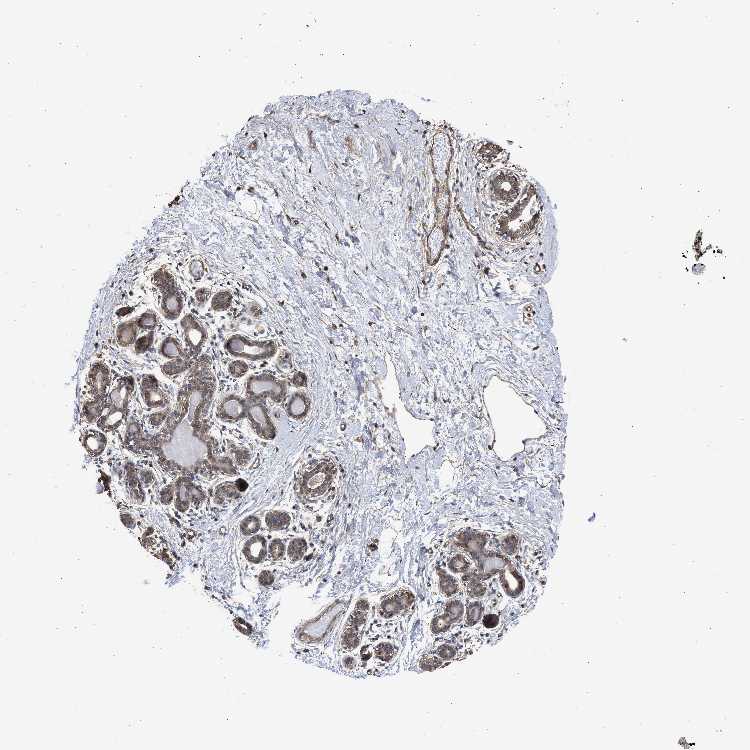

BREAST - Antibody stainingi

Antibody staining in the annotated cell types in the current human tissue is reported as not detected, low, medium, or high, based on conventional immunohistochemistry profiling in selected tissues. This score is based on the combination of the staining intensity and fraction of stained cells.

Each image is clickable and will lead to virtual microscopy that enables deeper exploration of all samples and also displays staining intensity scores, fraction scores and subcellular localization as well as patient and tissue information for each sample.

Antibody HPA017983

Adipocytes Not detected

Glandular cells Medium

Myoepithelial cells Medium